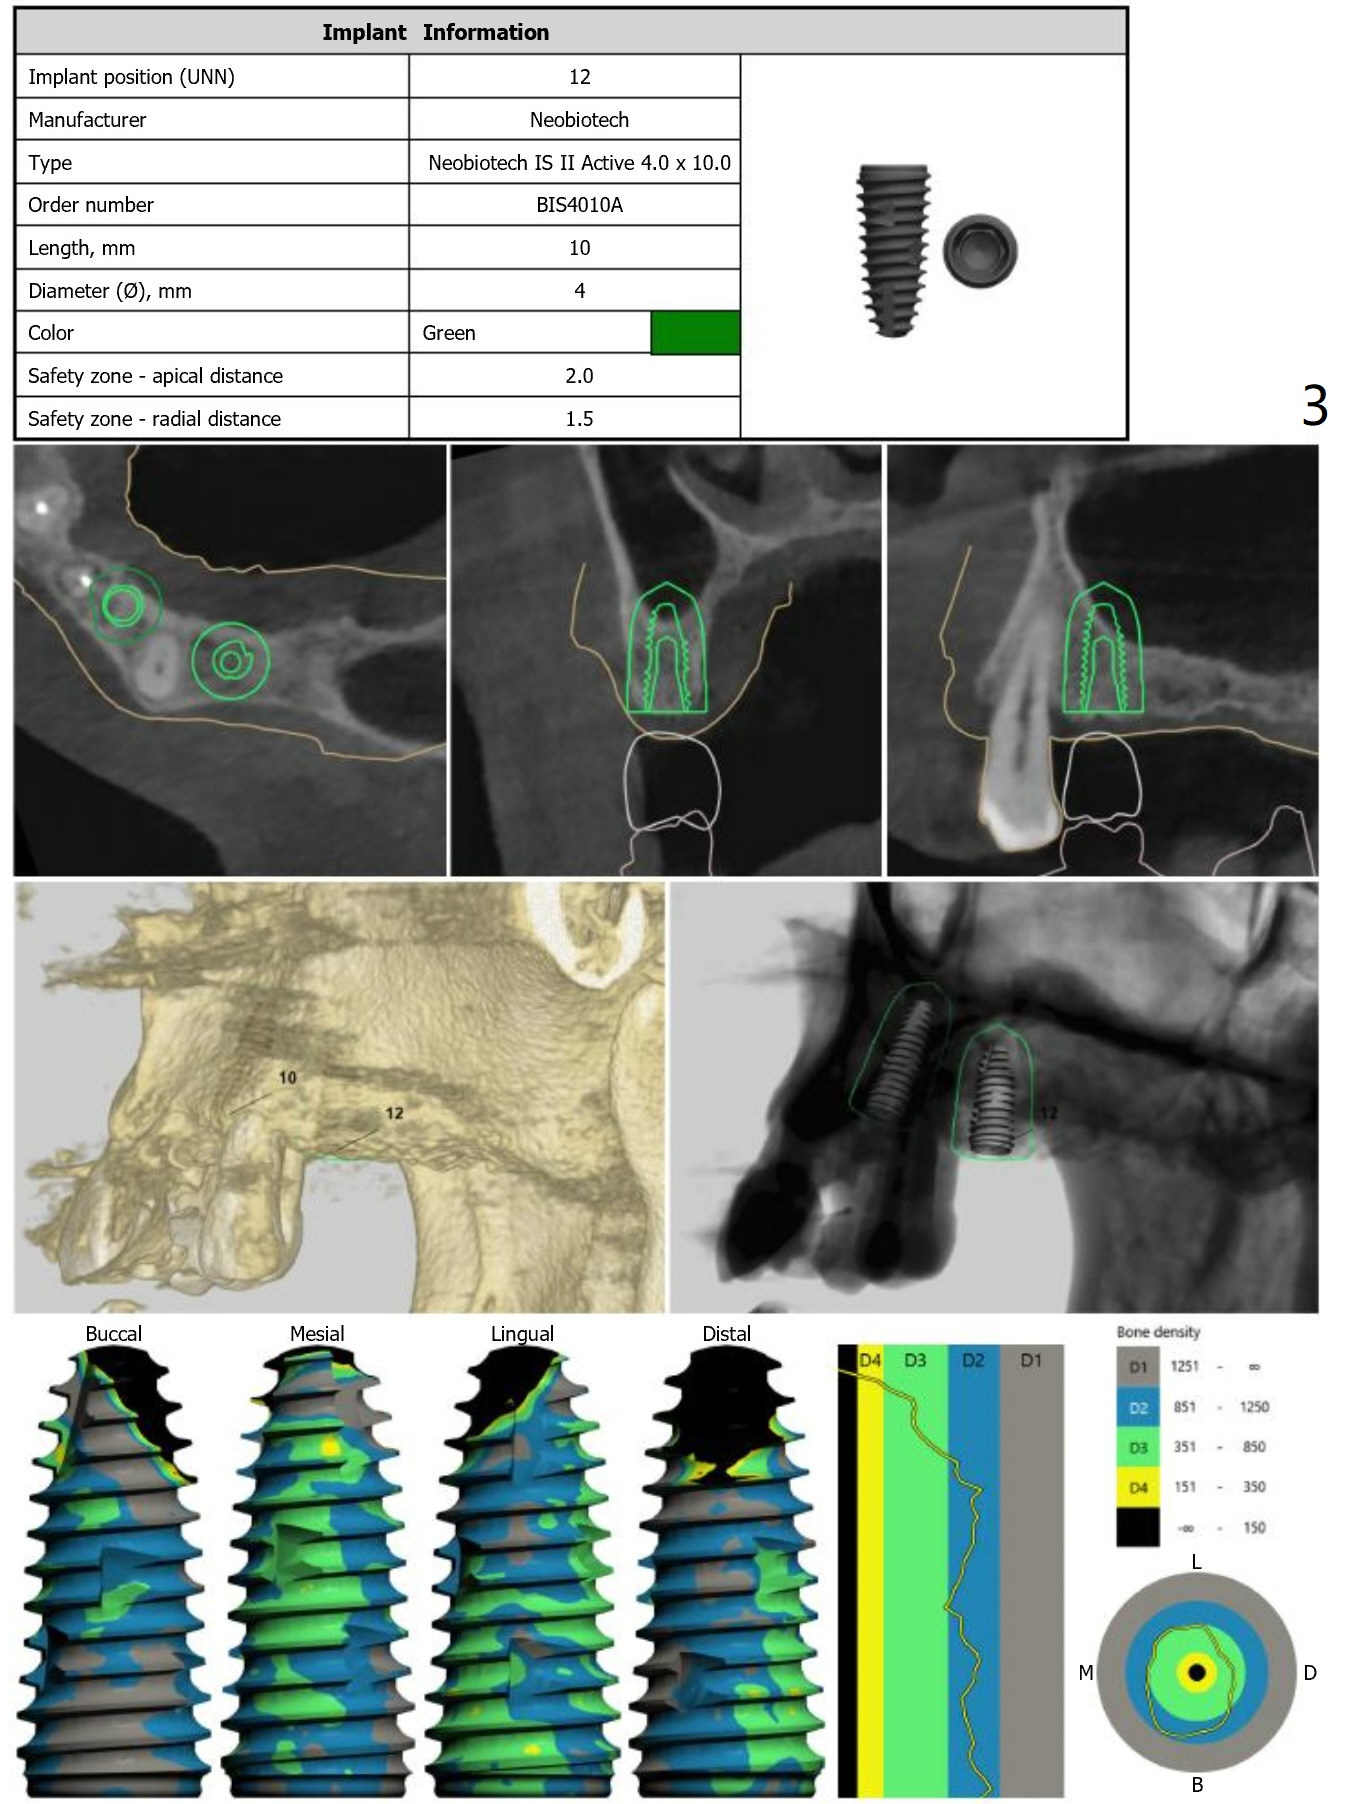

We have re-conducted the implant planning of this patient for #10 & 12.  This case requires both narrow navi guide kit and regular navi guide kit. And for #10, 2 surgical guides with different offsets will be sent.